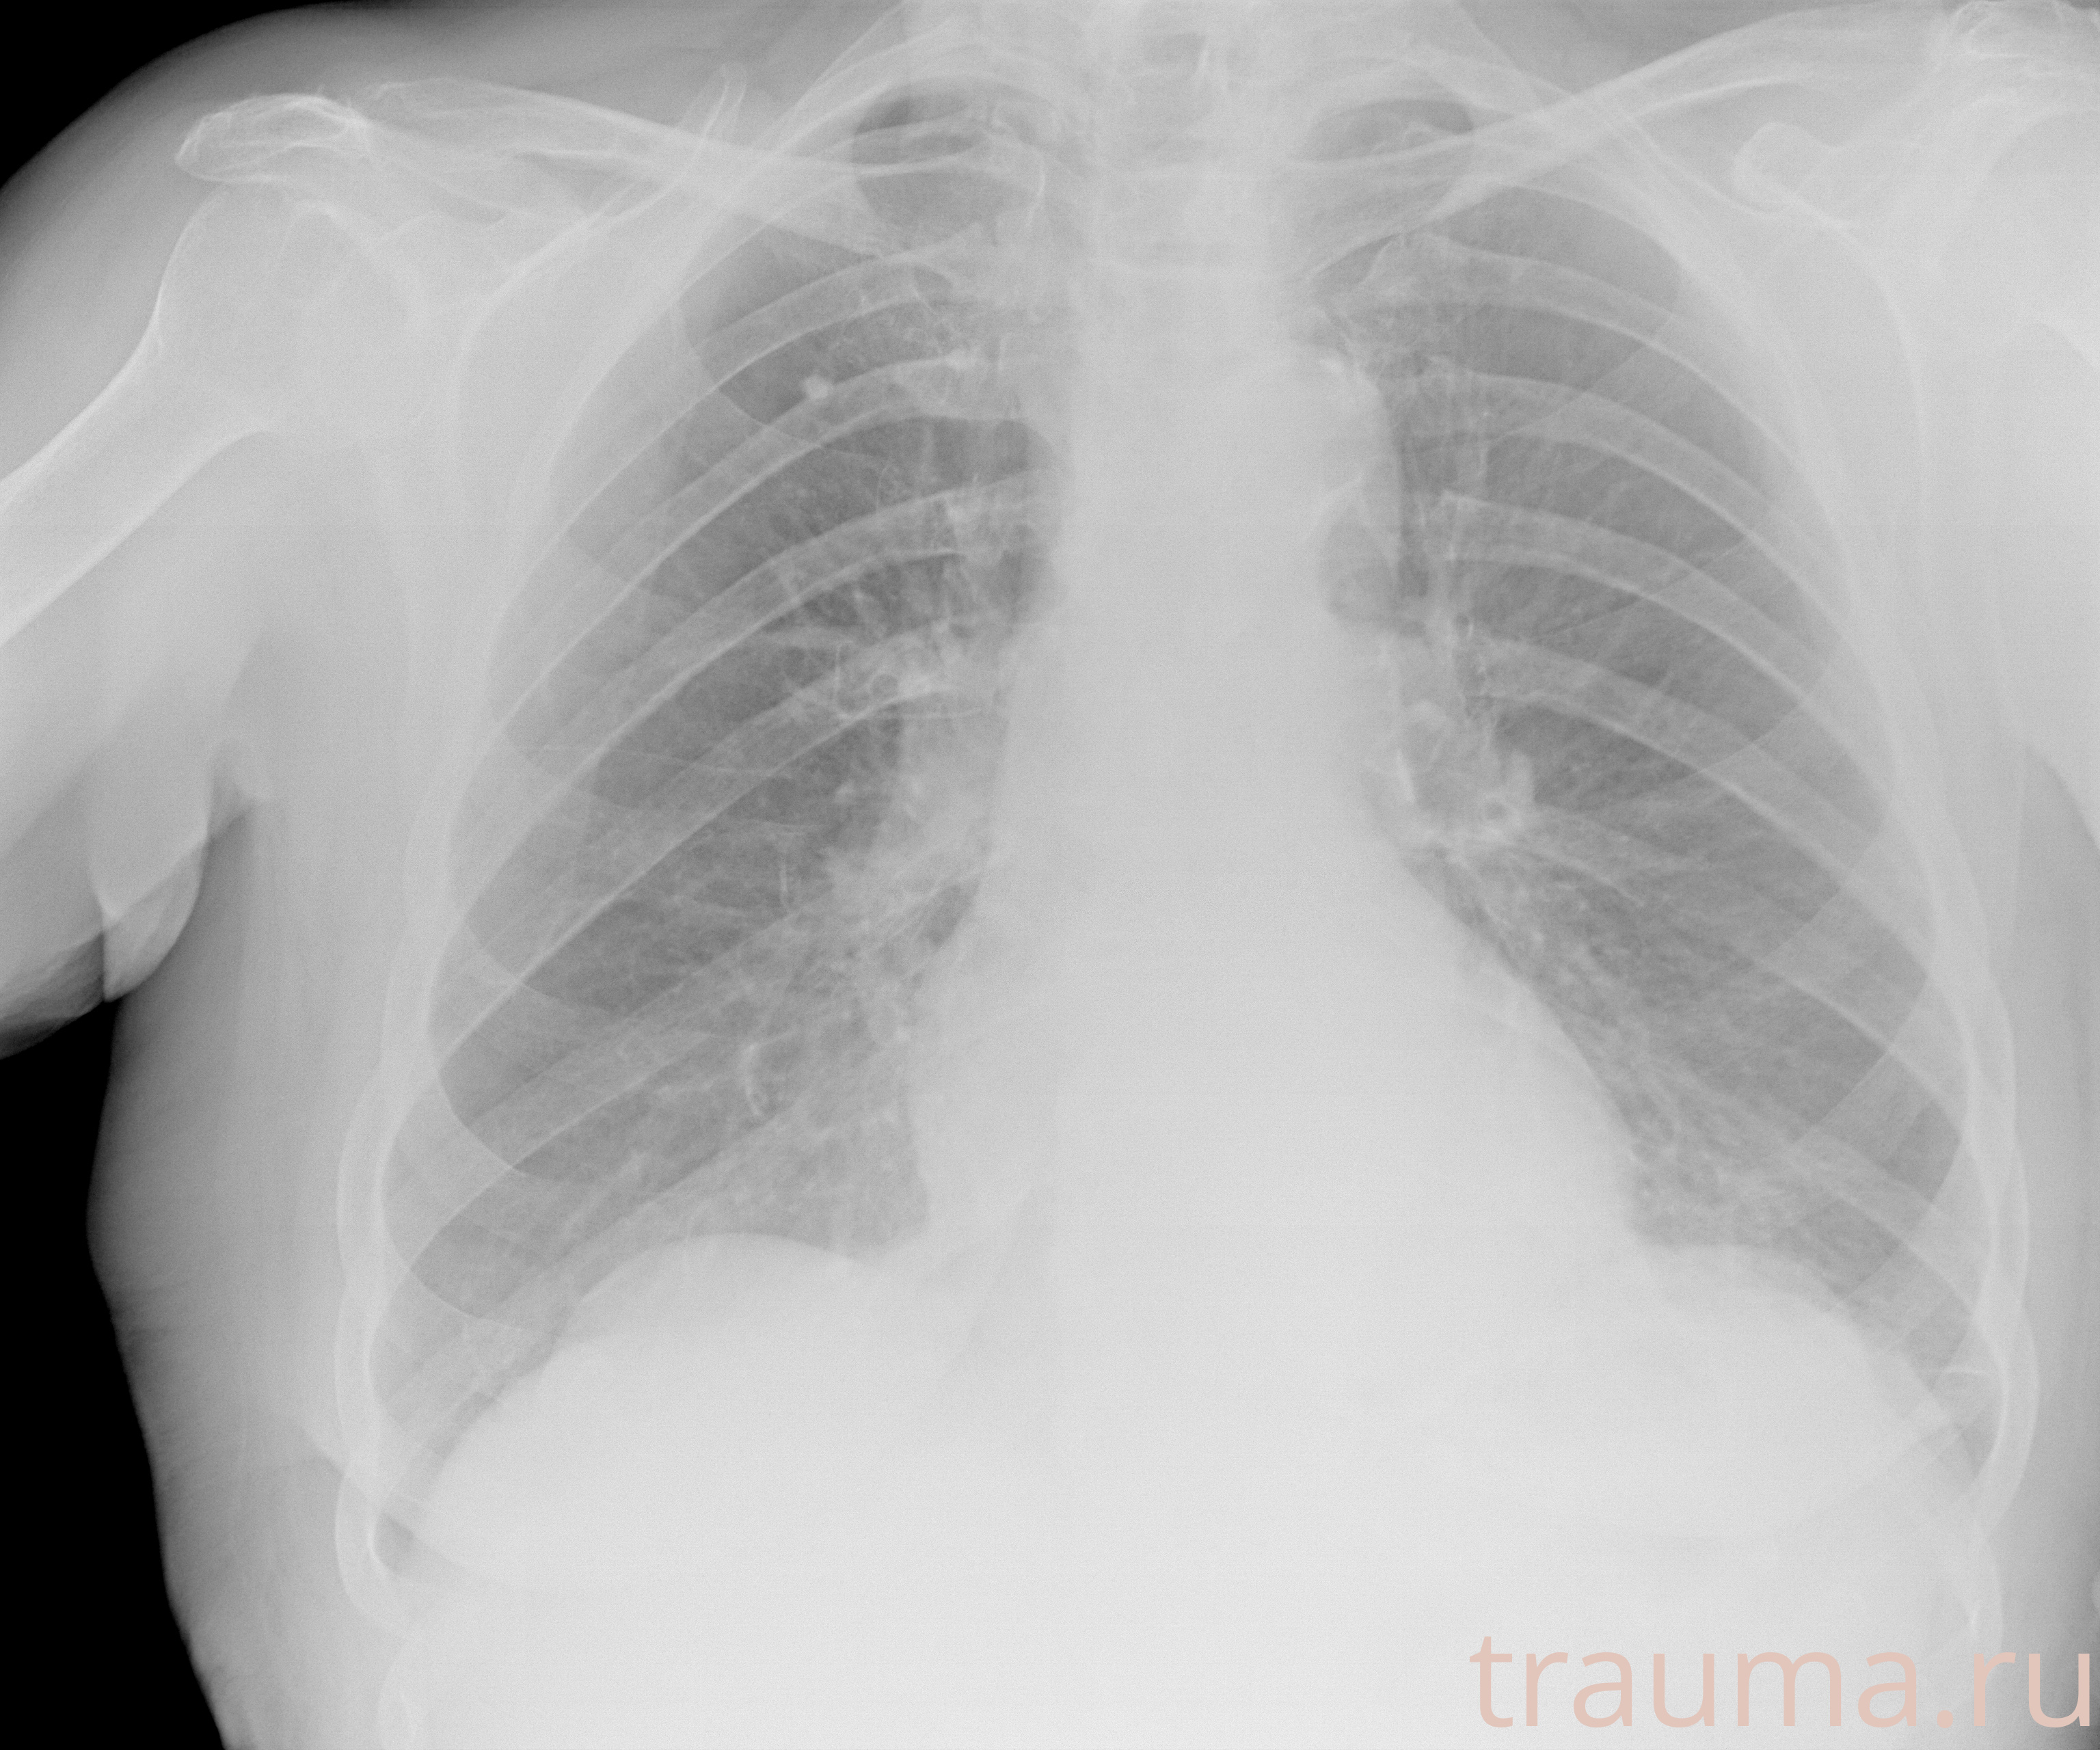

Рентгенограммы

Рентген на дому: по вашему адресу приезжает врач-рентгенолог, травматолог-ортопед с мобильным рентгеновским аппаратом, проводит диагностику травмы или заболевания, делает необходимые рентгенограммы, дает рекомендации по дальнейшему лечению. Получить качественные снимки в домашних условиях возможно благодаря уникальной методике, разработанной МосРентген Центром для института  Склифосовского

при переломе шейки бедра и пневмонии от компании МосРентген Центр - партнера Института имени Склифосовского